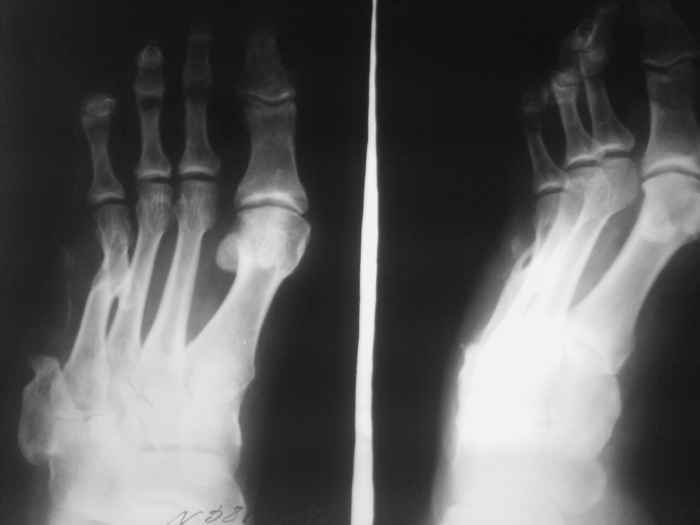

Остеомиелит 4 плюсневой кости. |

Мужчина 50 лет. Оперирован 2 года назад. Удален 5 луч по поводу инфицированного открытого перелома.

Жалобы на упорные боли и образование свища при нагрузке на латеральной поверхности стопы в области п/о рубца. Свищ открывается примерно 6 раз за год.

На момент осмотра свищевой ход закрыт. Воспаления м.тк. нет.